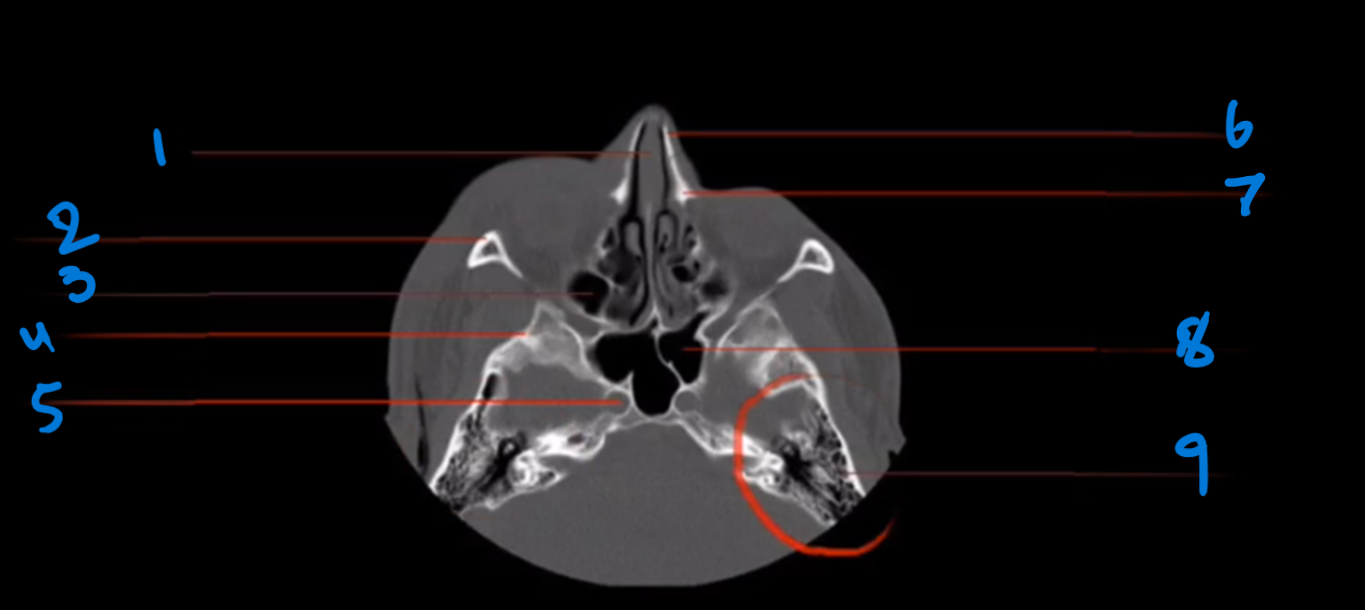

Landmark 1?

Maxillary Bone

Landmark # 2

Maxillary sinus

Landmark #3?

Coronoid process, mandible

Landmark # 4 called?

Mandibular condyle

Landmark # 5?

Carotid Canal

Landmark # 6?

Jugular Foramen

Landmark # 7?

Nasal Septum

Landmark # 8

Nasolacrimal duct

Landmark # 9

Zygoma

Landmark # 10

Zygomatic arch

Landmark # 11?

Clivus

Landmark # 12

External Auditory Meatus

Landmark # 13

Mastoid Air Cells, Temporal Bone